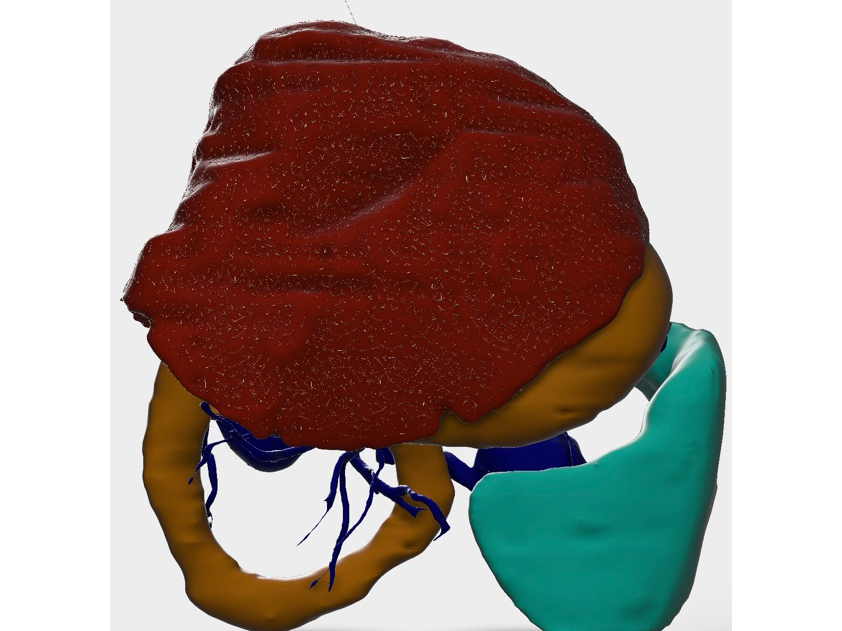

CT検査のデータを3D画像化し血管走行等を把握